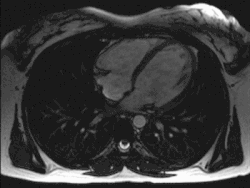

Das Herz liegt innerhalb des Herzbeutels (Perikard) im Mediastinum: Seitlich grenzen, getrennt durch parietale und viszerale Pleura (Brustfell), die linke und rechte Lunge an das Herz. Unten sitzt das Herz dem Zwerchfell auf, das mit dem Herzbeutel verwachsen ist. Oberhalb teilt sich die Luftröhre (Trachea) in die beiden Hauptbronchien (Bifurcatio tracheae), von denen der linke vom Aortenbogen überquert wird. Unterhalb dieser Aufteilung befindet sich der linke Herzvorhof. Wenn dieser krankhaft vergrößert ist, kann das zu einer Spreizung der Hauptbronchien führen, was sich im Röntgenbild als vergrößerter Winkel zwischen den Bronchien darstellt. Der linke Vorhof steht außerdem nach hinten in direktem Kontakt mit der Speiseröhre. Vor dem Herzen befindet sich das Brustbein (Sternum), im oberen Bereich liegt es vor den abgehenden großen Gefäßen. Zwischen Brustbein und Herz liegt der Thymus.

Das Herz liegt also praktisch direkt hinter der vorderen Leibeswand in Höhe der zweiten bis fünften Rippe. Die Herzbasis oben reicht nach rechts etwa zwei Zentimeter über den rechten Brustbeinrand hinaus. Unten kommt die Herzspitze knapp an eine gedachte senkrechte Linie heran, die durch die Mitte des linken Schlüsselbeins verläuft (linke Medioklavikularlinie).

Anatomie

Die Gestalt des Herzens gleicht einem abgerundeten Kegel, dessen Spitze nach unten und etwas nach links vorne weist. Das Herzvolumen entspricht ungefähr dem Volumen der geschlossenen Faust[19] des betreffenden Menschen. Das Herz sitzt beim Menschen in der Regel leicht nach links versetzt hinter dem Brustbein. In seltenen Fällen ist es nach rechts versetzt (die sogenannte Dextrokardie – „Rechtsherzigkeit“), meist bei Situs inversus (also bei spiegelverkehrter Organanordnung).